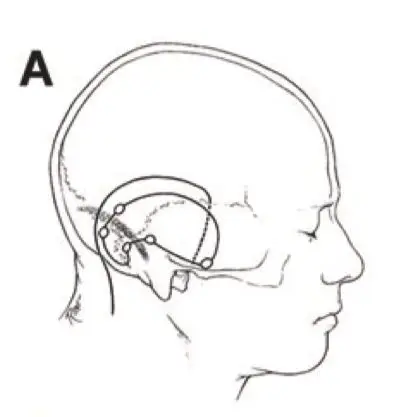

针对岩斜区肿瘤的手术理念和入路选择存在多种方案,包括额颞入路、枕下小脑幕入路、颞下小脑幕入路、颞下入路以及耳蜗入路等。但对于体积巨大的肿瘤或同时向幕上幕下生长的肿瘤,INC国际...